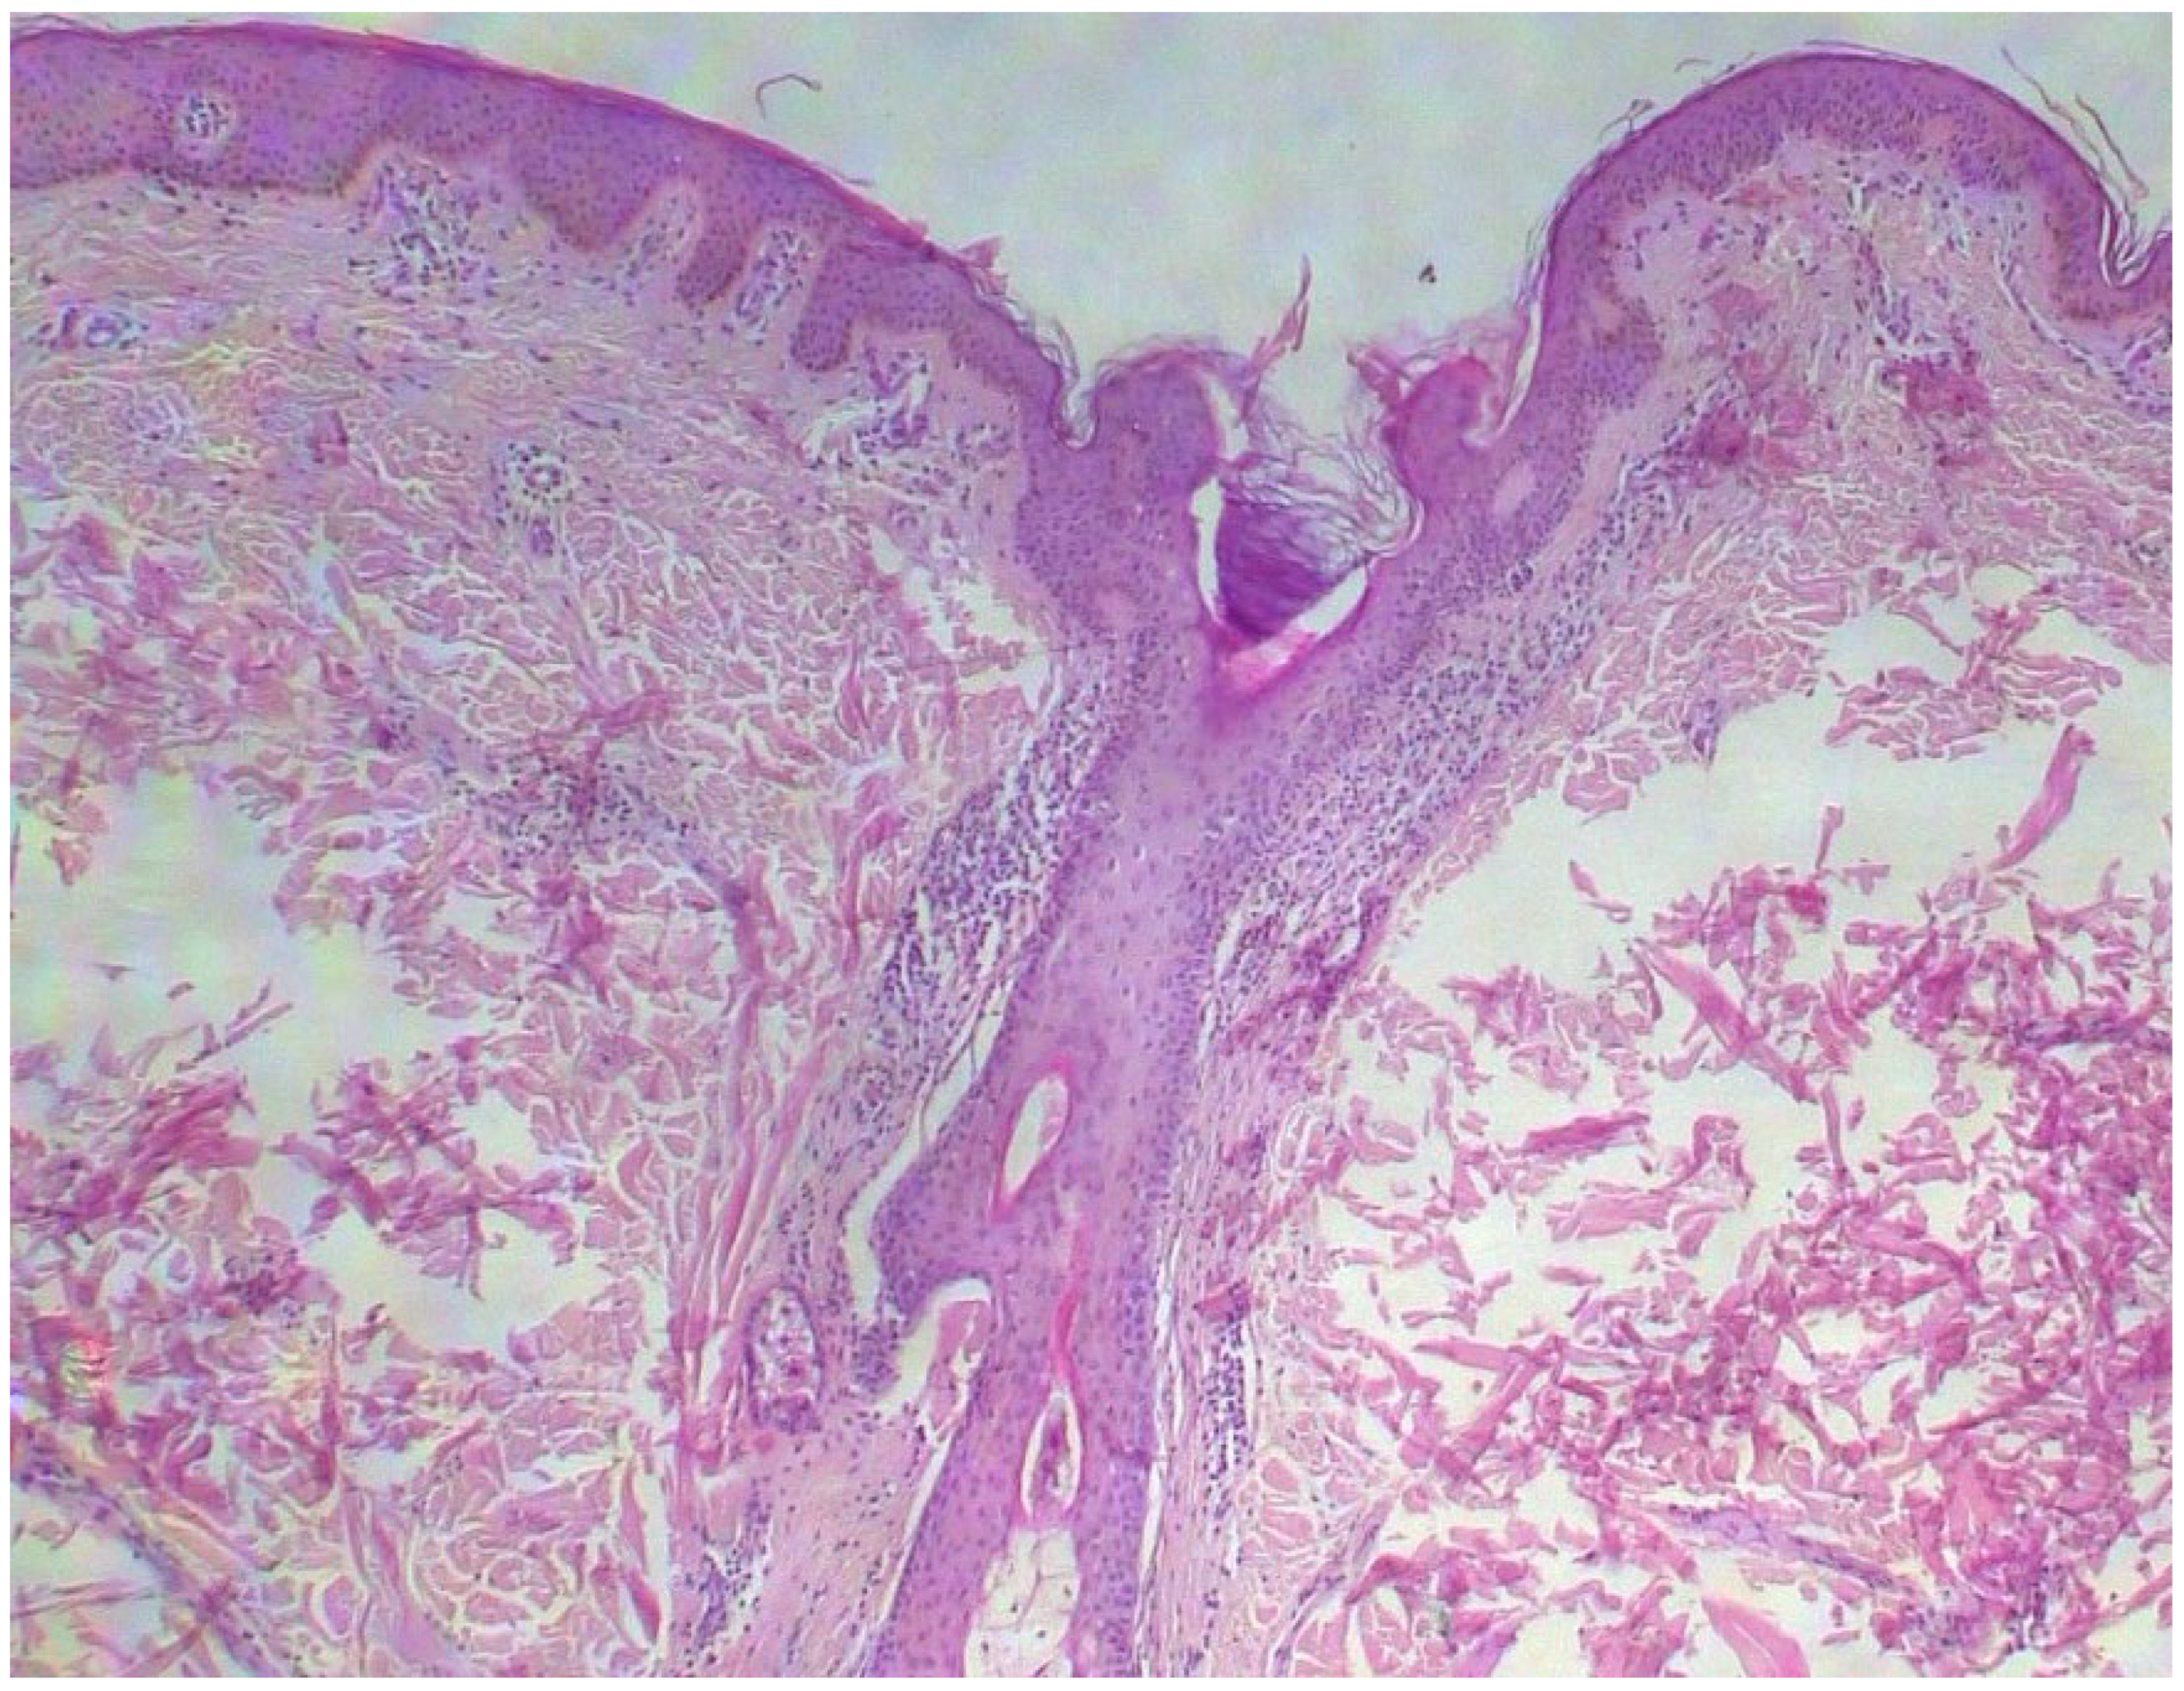

A skin biopsy showed basal cell hyperpigmentation and a chronic superficial perivascular inflammatory infiltrate that also affected the periphery of the hair follicles (Figure 6). Tryptase stain reached figures of up to 29 mast cells per high-power view (67/mm2), and CD117 up to 46 mast cells per high-power view (92/mm2), mostly surrounding the hair infundibulum (Figure 7), although some interstitial mast cells were also observed (Figure 8). PAS stain was negative for yeasts or fungal hyphae. Abdominal ultrasound study did not detect any anomalies. The bone scintigram detected mild non-specific osteoblastic lesions in the L5, S1 and sacroiliac joints (pending further study).

Figure 6. Basal cell pigmentation and superficial dermal inflammatory infiltrate, mostly surrounding the pilosebaceous infundibulum (HE ×40).